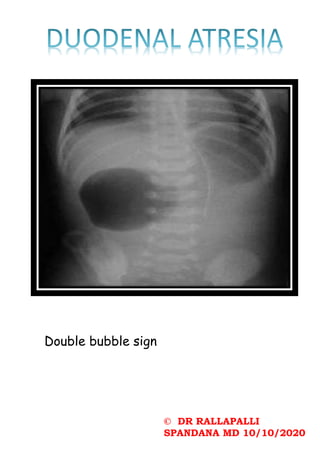

Double bubble sign

© DR RALLAPALLI SPANDANAMD 10/10/2020 Double bubble sign